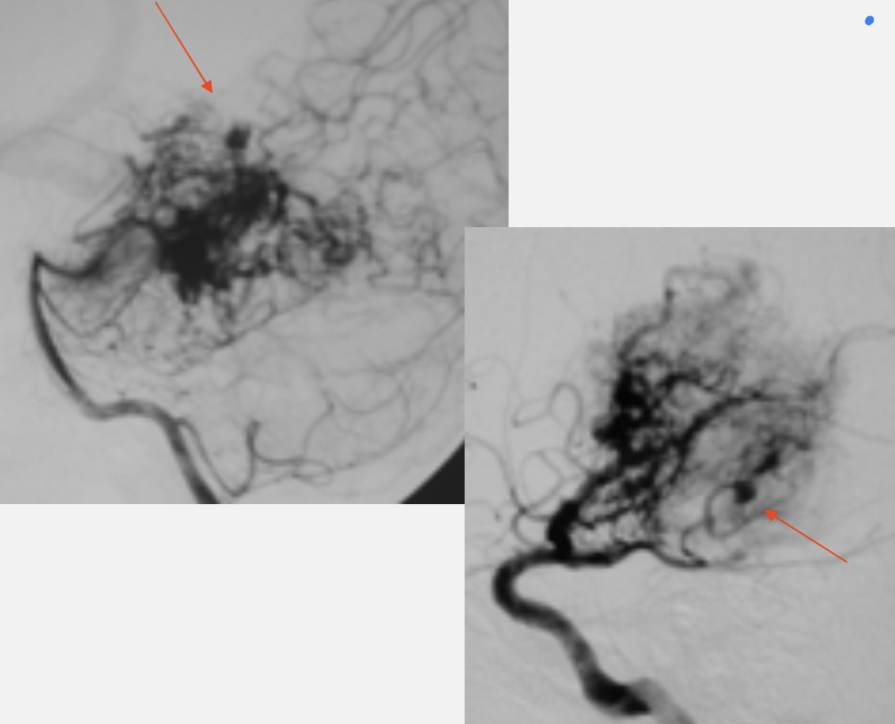

AVM - architecture

AVM - nidus:

AVM - topography and vessels involved